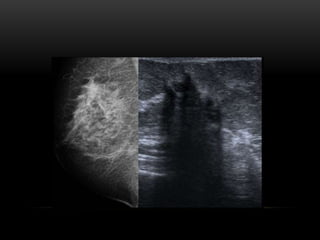

ULTRASONIDO

• Mamas densas

• Caracterización de nódulo palpable mastográficamente no

visible

• Caracterización de nódulo mastográficamente visible

• Caracterización de asimetría focal

• Aplicación de Doppler

• Biopsia

PATRÓN DEL TEJIDO GLANDULAR

ECOGRÁFICO:

1. Ecoestructura homogénea grasa

2. Ecoestructura homogénea

fibroglandular

3. Ecoestructura heterogénea